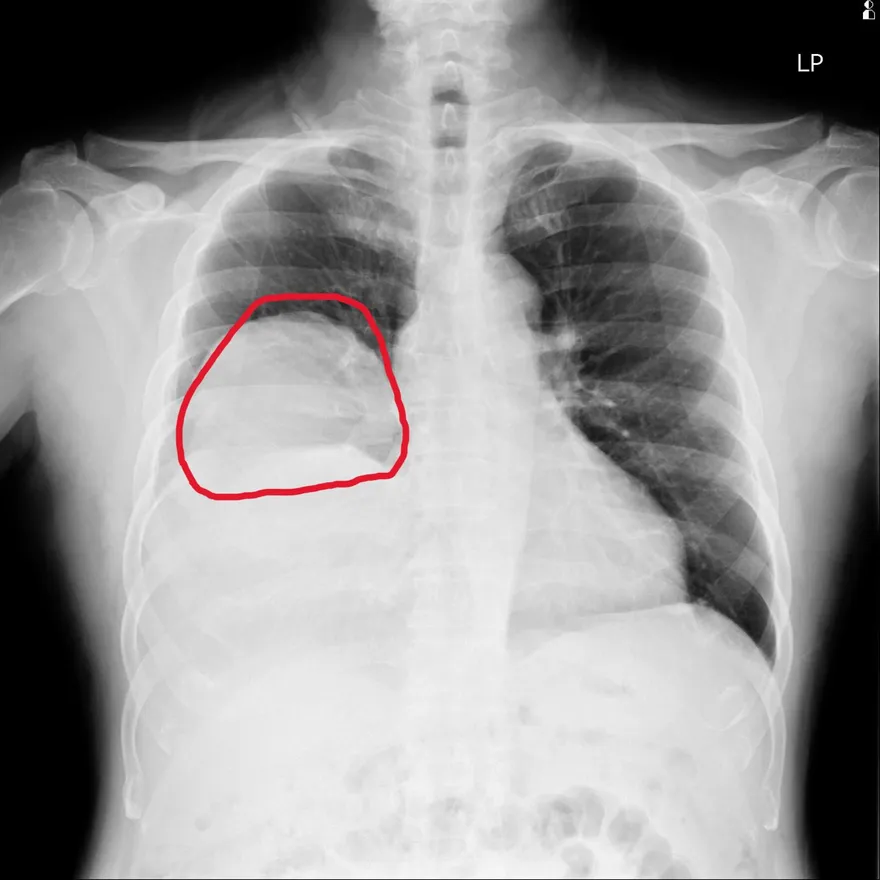

反覆昏迷血糖僅30!7旬翁肺裡藏顆「25公分大腫瘤」